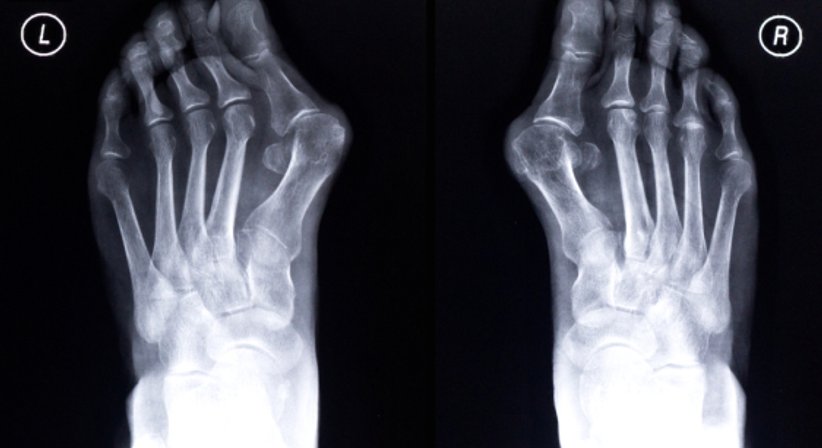

Hallux Valgus

Für die operative Behandlung des Hallux valgus (Fehlstellung der Großzehe) stehen mehrere Operationsverfahren zur Wahl, darunter die Operation nach Bösch und die Operation nach Austin (Chevron-Osteotomie). Ziel einer Hallux valgus-Operation ist, neben der Abtragung des störenden Überbeins, das Wiederherstellen der Funktion des Großzehengrundgelenks und regulärer Achsverhältnisse.